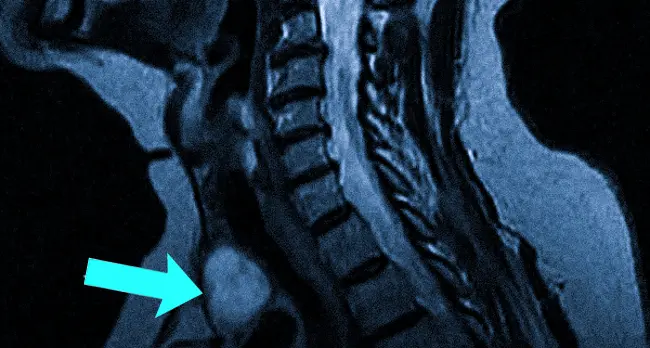

Новообразование (указано стрелкой) на МРТ щитовидной железы

Тиреоидиты – воспалительные процессы, которые могут иметь инфекционную и аутоиммунную природу. Автоиммунные тиреоидиты встречаются чаще и зачастую протекают в хронической форме. В некоторых случаях симптомы могут отсутствовать, а в других может наблюдаться легкое увеличение органа. При развитии гипотиреоза возникают симптомы, характерные для недостатка гормонов щитовидной железы. Среди врожденных аномалий выделяют: